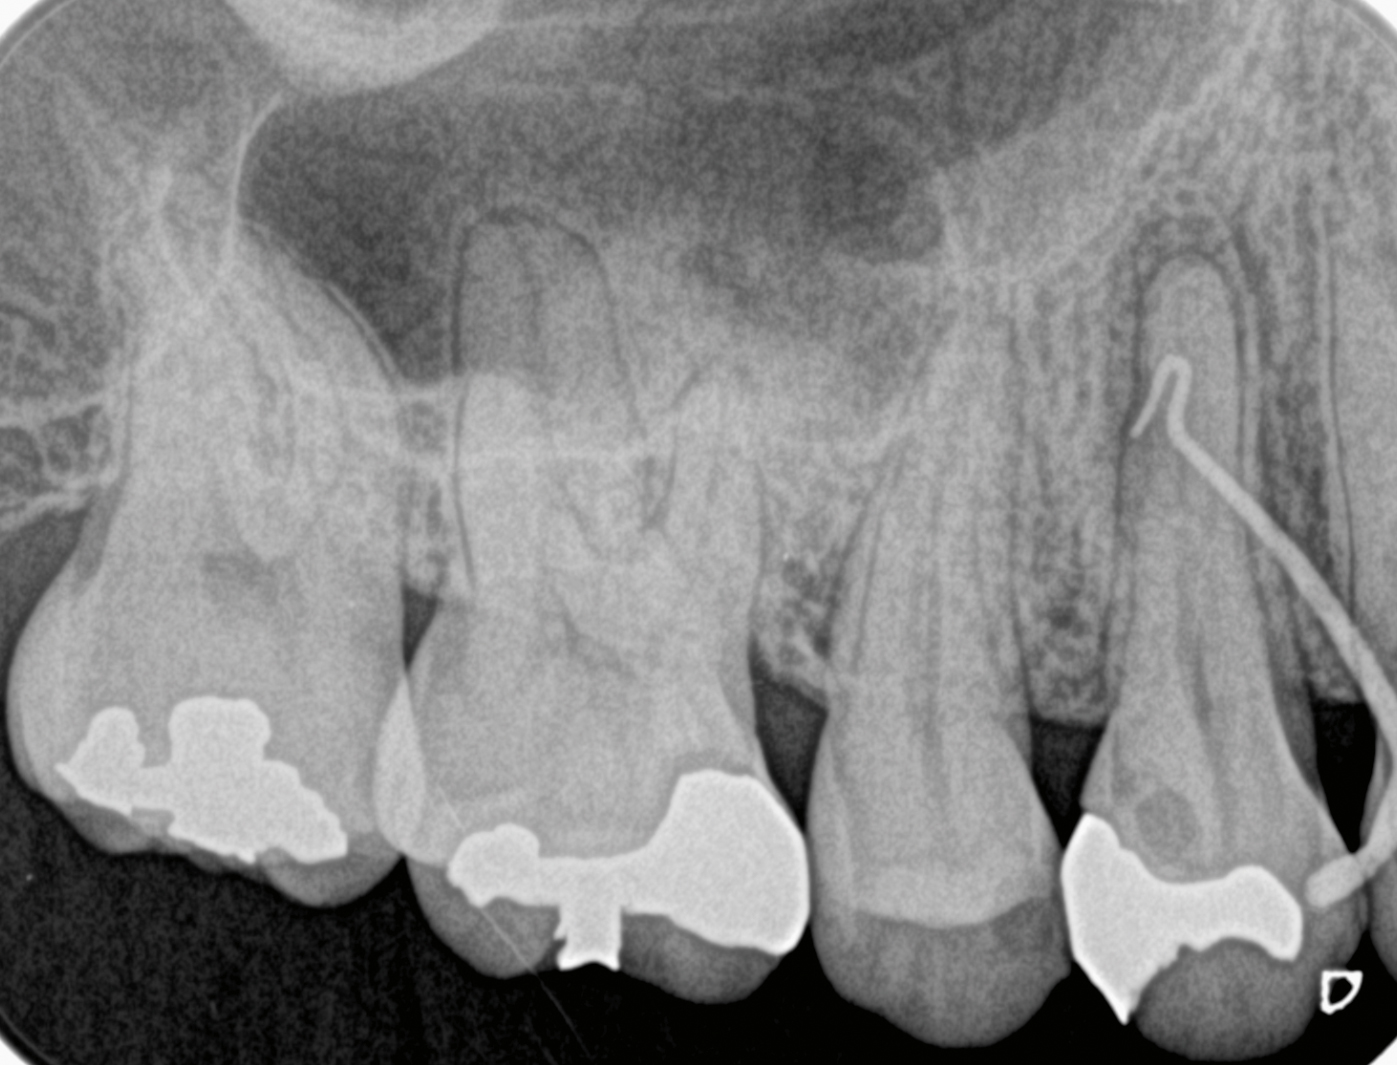

右上4番瘻孔を伴う歯髄壊死症例。瘻孔部分にガッタパーチャポイントを挿入している。